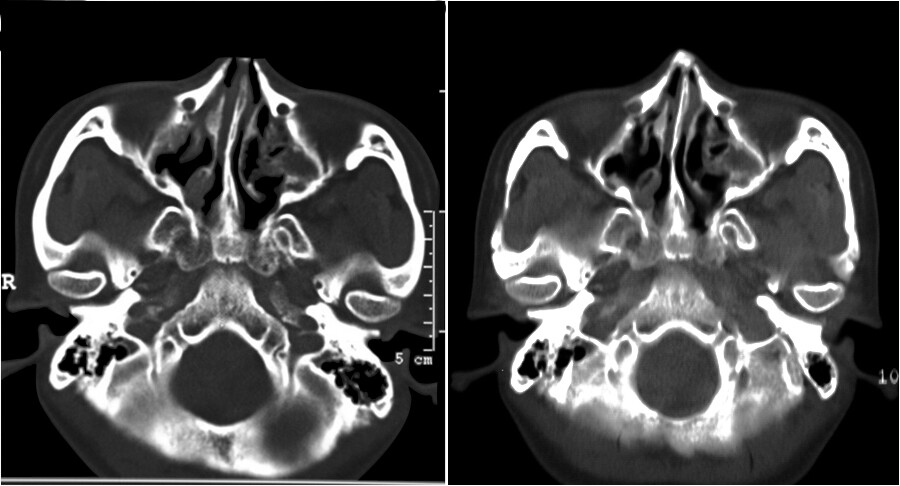

随访时间为 3~30 个月,平均 12.5 个月。所有缩窄后的颧弓均结构稳定,患者面部均如期变窄,未出现反弹现象。对 119 侧颧弓在术后 6~12 个月 进行了CT复查,所有颧弓影像均呈自然外观,颧弓高度理想性降低(见图6)。

图6在颧弓水平的横断面CT图像显示了多点截骨颧弓缩窄颧骨整形后的变化。左图为术前影像,右图为同一患者术后一年影像。